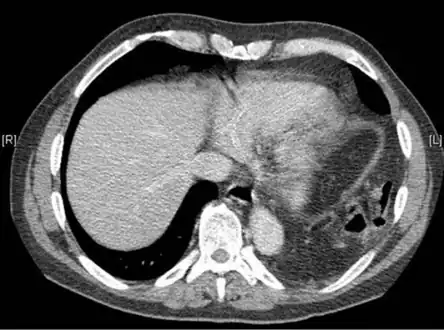

Physical examinations are not accurate, as there is usually no specific physical sign that can be used to diagnose this condition.[6] Thoracoscopic and laparoscopic methods can be accurate.[15] Chest X-ray is known to be unreliable in diagnosing diaphragmatic rupture;[7] it has low sensitivity and specificity for the injury.[8] Often another injury such as pulmonary contusion masks the injury on the X-ray film.[9] Half the time, initial X-rays are normal; in most of those that are not, hemothorax or pneumothorax is present.[7] A nasogastric tube from the stomach may appear on the film in the chest cavity; this sign is pathognomonic for diaphragmatic rupture, but it is rare.[7] The X-ray is better able to detect the injury when taken from the back with the person upright, but this is not usually possible because the person is usually not stable enough; thus it is usually taken from the front with the person lying supine.[8] Positive pressure ventilation helps keep the abdominal organs from herniating into the chest cavity, but this also can prevent the injury from being discovered on an X-ray.[7]

A CT scan has an increased accuracy of diagnosis over X-ray,[10] but no specific findings on a CT scan exist to establish a diagnosis.[12] The free edge of a ruptured diaphragm may curl and become perpendicular to the chest wall, a sign known as a dangling diaphragm. A herniated organ may constrict at the location of a rupture, a sign known as the collar sign. If the liver herniates through a rupture on the right side, it may produce two signs known as the hump and band signs. The hump sign is a form of the collar sign on the right. The band sign is a bright line that intersects the liver. it is believed to result due to the ruptured diaphragm compressing.[16] Although CT scanning increases chances that diaphragmatic rupture will be diagnosed before surgery, the rate of diagnosis before surgery is still only 31–43.5%.[10] Another diagnostic method is laparotomy, but this misses diaphragmatic ruptures up to 15% of the time.[7] Often diaphragmatic injury is discovered during a laparotomy that was undertaken because of another abdominal injury.[7] Because laparotomies are more common in those with penetrating trauma than compared to those who experienced a blunt force injury, diaphragmatic rupture is found more often in these people.[17] Thoracoscopy is more reliable in detecting diaphragmatic tears than laparotomy and is especially useful when chronic diaphragmatic hernia is suspected.[7]

Location

Between 50 and 80% of diaphragmatic ruptures occur on the left side.[8] It is possible that the liver, which is situated in the right upper quadrant of the abdomen, cushions the diaphragm.[9] However, injuries occurring on the left side are also easier to detect in X-ray films.[7] Half of diaphragmatic ruptures that occur on the right side are associated with liver injury.[8] Injuries occurring on the right are associated with a higher rate of death and more numerous and serious accompanying injuries.[13] Bilateral diaphragmatic rupture, which occurs in 1–2% of ruptures, is associated with a much higher death rate (mortality) than injuries that occur on just one side.[8]